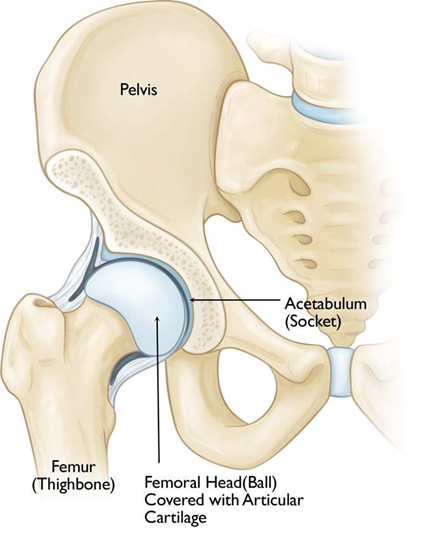

Hip osteoarthritis (OA) is a degenerative joint disease characterized by the gradual breakdown of cartilage in the hip joint. As the protective cartilage wears away, bones begin to rub against each other, leading to pain, stiffness, and reduced mobility. Affecting millions worldwide, hip OA significantly impacts quality of life, especially in older adults. However, advancements in conservative and regenerative therapies now offer hope for managing symptoms and slowing disease progression. This page explores the causes, risk factors, stages, and both traditional and cutting-edge treatment options for hip osteoarthritis, including when surgical interventions like total hip replacement become necessary.

Causes of Hip Osteoarthritis

Hip OA develops when the cartilage cushioning the joint deteriorates over time. Key causes include:

- Primary OA: Age-related "wear and tear" from repetitive stress on the joint.

- Secondary OA: Triggered by injury (e.g., fractures, dislocations), congenital abnormalities (e.g., hip dysplasia), inflammatory diseases (e.g., rheumatoid arthritis), or obesity.